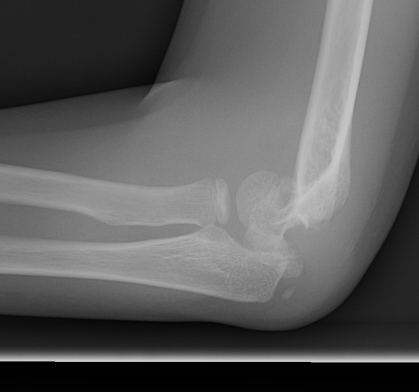

Gartland Classification Extension Fractures

Gartland I - Undisplaced

- < 2 mm

- anterior and posterior cortices intact

Gartland II - Displaced with intact posterior cortex

- > 2 mm

- anterior humeral line passess anterior to capitellum

- posterior periosteum is intact

Gartland III - Displaced, nil cortical contact

- completely displaced

- posteromedial or posterolateral

Gartland IV - Nil cortical contact with complete periosteal disruption

Extremely unstable at surgery in both flexion and extension planes